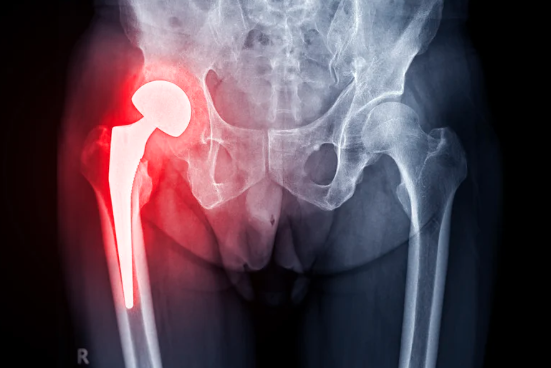

• 髖關節鏡手術(微創手術)

• 髖關節置換手術